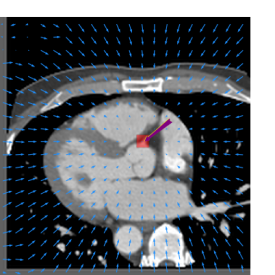

Finally, the proposed network was evaluated for the detection of five additional landmarks: the left coronary ostium, the bifurcation of the LM into the LAD and the LCx, and the origin of the left, non-coronary, and right aortic valve commissures (see Fig. 2). Fig 3 shows vector fields visualizing the predicted displacement vectors in three viewing planes in an image from the test set (for more results, see Appendix). Table 3 lists the Euclidean distance errors between the predicted landmark locations and the reference landmark locations. In addition, box-and-whiskers plots are shown in Fig 4. The best results were obtained for the origin of the right aortic valve commissure. Detection of the origin of the left aortic valve had the most narrow distribution. Outliers were seen during detection of the right ostium, the bifurcation of the LM, and the origin of the non-coronary, and the left aortic valve commissure.

Refer to caption Refer to caption Refer to caption

Figure 3: Vector fields visualizing the predicted displacement vectors in the axial, coronal, and sagittal plane in an image from the test set where detection of the right coronary ostium was performed. The magnitudes of the vectors should point at the right ostium, but they are rescaled for visualization purposes. The red squares indicate posterior probabilities larger than 0.5, obtained by the classification network for image patches. Reference and computed landmark annotations are indicated with a yellow and purple arrow, respectively.

Refer to caption Refer to caption Refer to caption Refer to caption Refer to caption Refer to caption Refer to caption Refer to caption Refer to caption Refer to caption Refer to caption Refer to caption Refer to caption Refer to caption Refer to caption Refer to caption Refer to caption Refer to caption

Figure 2: Vector fields visualizing the predicted localization vectors in the axial, coronal, and sagittal planes in images from the test set. The magnitudes of the vectors should point at the ostia, but they are rescaled for visualization purposes. The red squares indicate posterior probabilities that are larger than 0.5, obtained by the classification network for image patches. Reference and computed landmark annotations are indicated with a yellow and purple arrow, respectively. From the top to the bottom row, results are shown for detection of the right and left coronary ostium, the bifurcation of the LM, and the origin of the right, non-coronary, and left aortic valve commissure, respectively.